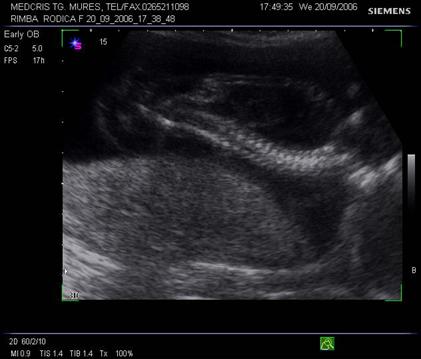

Fig . nr. 244 Higroma cystic la o sarcina cu anasarca , cu fat mort intrauterin, cu lungimea femurului corespunzatoare la 17 sapt. , sectiune longitudinala

Fig nr. 245. Higroma cystic, la aceeasi sarcina, sectiune transversala

Fig nr.246. Angularea coloanei vertebrale la fatul mort intrauterin , cu higroma cystic si hidrops

Fig. nr. 247 . Aceeasi sarcina ca in figurile precedente, se remarca atit ascita cat si edemul masiv subcutanat